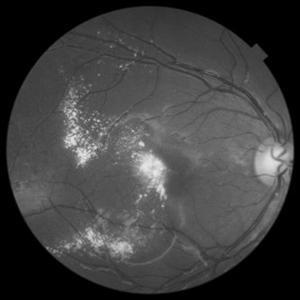

Red Free Photograph of an 18-Year-Old Female with Coats' Disease

Mar 4 2017 by Hashim Ali Khan, OD, FAAO

Aneurysms, TEL and exudation.

Condition/keywords: aneurysm, Coats' disease, exudate, light-bulb aneurysms